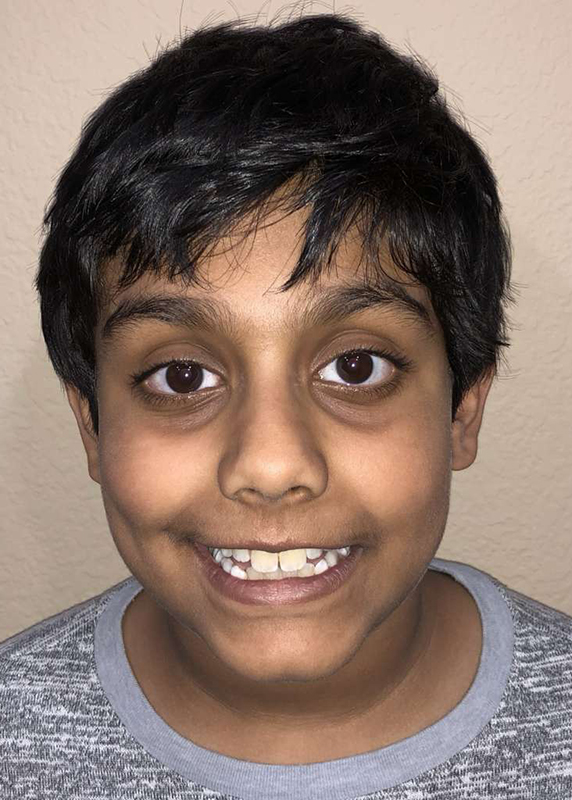

Actual Patient: Arjun

Before

Severe crowding, narrow jaws, deep bite